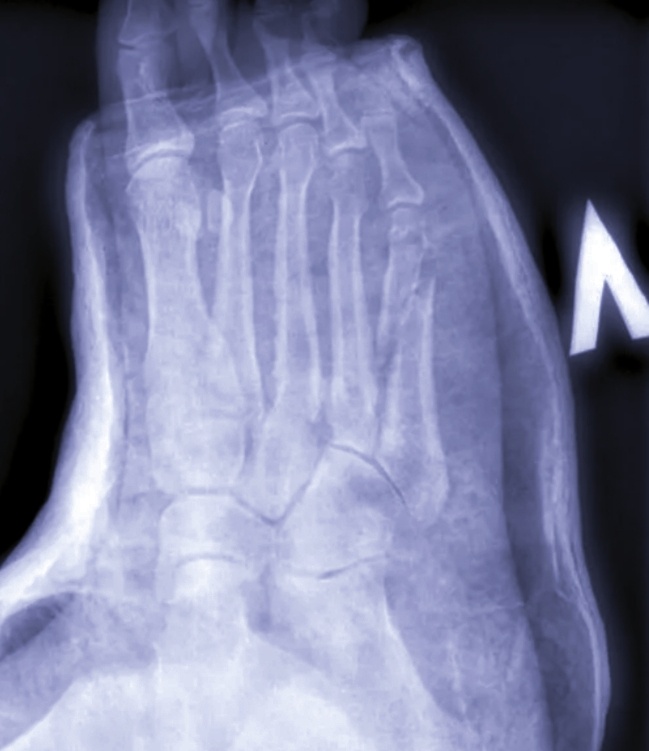

Пятая плюсневая сломана.

Мало режима дала ! Да что ж они в последнее время такие толстенные гипсы накладывают! Ноь, видно , что в двух местах сломана косточка.

–Колесико -то большое было что ли?-спрашиваю, –В двух местах сломали.